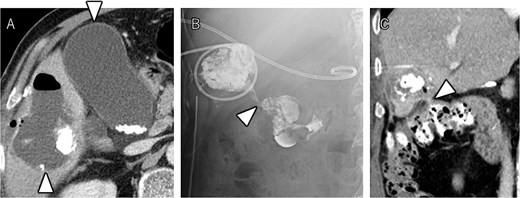

After seven courses of treatment, he was transported to our emergency department because of abdominal pain. CT revealed ascites and free air on the liver surface as well as air within the liver tumor (Fig. 3). Peritonitis was diagnosed, and emergency laparotomy was performed. Strong adhesions were observed between the liver tumor, greater omentum, and the colon. Although small amounts of turbid ascites were found, no obvious perforations were observed in the stomach, duodenum, or small intestine. Abdominal lavage and drainage were performed. Postoperatively, persistent fever and elevated levels of inflammatory markers were noted. Subsequent CT revealed a fluid collection with air within the liver tumor and thickening of the gallbladder wall (Fig. 4A). The patient was diagnosed with a liver abscess secondary to HCC necrosis and cholecystitis, and percutaneous transhepatic drainage of the liver abscess and gallbladder was performed. Seven days after the drainage, fistulography through the liver abscess drainage catheter revealed colonic opacification (Fig. 4B). CT revealed the liver tumor adjacent to the catheter with opacification of the colonic lumen (Fig. 4C). Based on these findings, a diagnosis of hepatocolic fistula secondary to HCC was made. Considering the low likelihood of natural closure, loop ileostomy was performed 13 days after the initial surgery to improve the patient’s systemic condition, but fistulography showed no improvement. As a definitive treatment for the persistent hepatocolic fistula, salvage surgery of hepatectomy with concomitant colectomy was planned 25 days after the initial surgery. Intraoperatively, the liver tumor, colon, and greater omentum were adhered together as a single mass (Fig. 5). After partial diaphragm resection and hepatic lobe mobilization, extended posterior sectionectomy and right hemicolectomy achieved complete tumor removal without macroscopic residual disease. Macroscopically, the liver tumor showed extensive necrosis (Fig. 6A). Histologically, the majority of the tumor consisted of necrotic tissue with hemorrhage and inflammatory infiltration (Fig. 6B). Areas of disrupted trabecular structures with proliferative cancer cells were still visible, consistent with HCC (Fig. 6C). Colonic mucosa was identified within the fistula, unequivocally confirming the communication between the tumor and the colon (Fig. 6D). However, no significant abscess formation was observed in this area, reinforcing the hypothesis that the necrosis-induced weakening of the tumor boundary played a central role in the development of the fistula. No postoperative complications occurred and the patient was discharged on postoperative Day 37. Nine months postoperatively, the patient continued ATZ + BV therapy under the care of our department. The patient’s clinical course is summarized in the time series diagram (Fig. 7).

CT demonstrating a fluid collection with air inside the liver tumor, as well as enlargement and wall thickening of the gallbladder (A). Fistulography performing through the liver abscess drainage catheter revealed contrast filling in the colon (B). Subsequent CT scan showed that the liver tumor was adjacent to the catheter, with opacification of the colonic lumen (C).